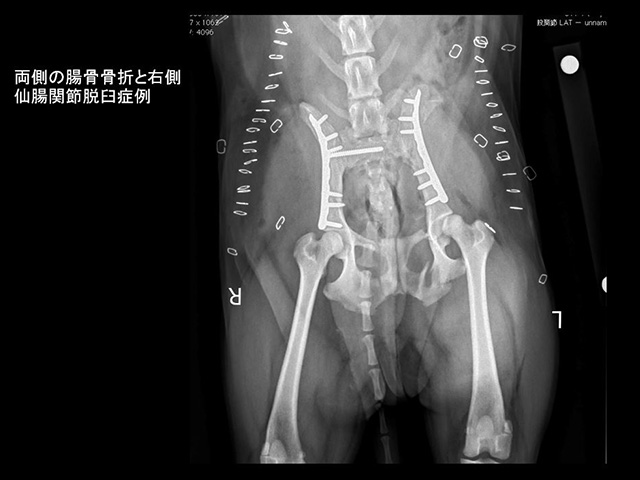

③ 骨盤骨折

交通事故などの大きな外力により骨盤を構成する腸骨や坐骨、恥骨、仙骨に生じます。骨盤は四角い箱状の形状を有し、内腔に腸管や膀胱と尿管、後肢に分布する血管などの重要な臓器を含みます。これらの臓器の障害を最小限にとどめ、回復されるために、早期の整復固定が必要となります。骨折の原因により、多くの骨片が生じる粉砕骨折の場合が一般的であり、手術前に3D-CTを駆使した状況確認を行います。特に寛骨臼(股関節の一部)の粉砕骨折では、必須検査となります。